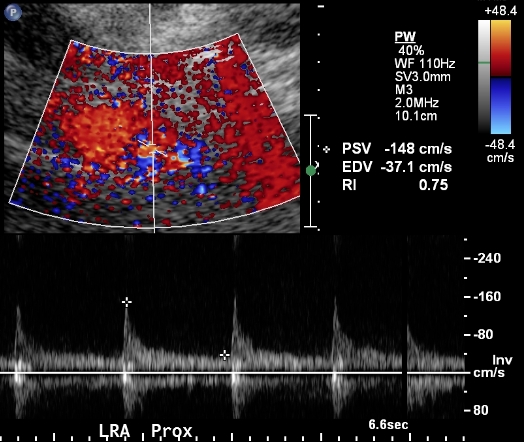

The next step is to identify the renal arteries. Each renal artery should be sampled in its origin and proximal, mid and distal portions. The distal portion of the renal artery is often difficult to obtain from the midline even in easy renal artery ultrasound. The proximal portion is difficult to obtain from the flank and therefore effort should be made to obtain it from the midline.

Sampling from the renal artery should be performed with angle correction.

A high-quality renal artery ultrasound will repeat similar measurements from both the midline and the flank approach. If there is great discrepancy between these measurements, it may mean that one of them is wrong.